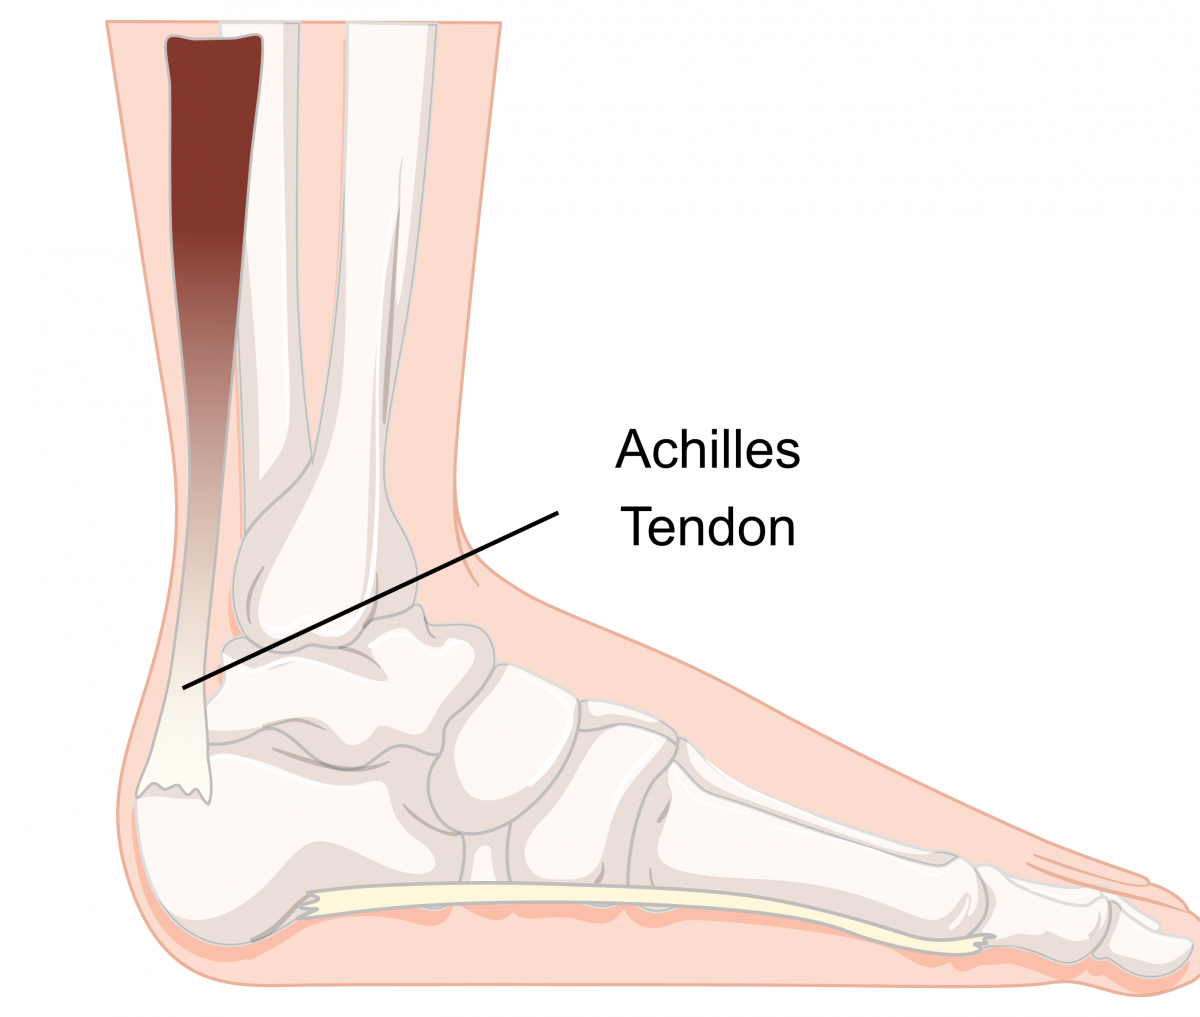

pictures of achilles tendon

Achilles Tendon – Squat University

Achilles Tendonitis Basics | Florida Orthopaedic Institute

Achilles Tendinitis Info | Florida Orthopaedic Institute

Achilles Tendonitis Basics | Florida Orthopaedic Institute

Achilles Tendon – NJSM

Achilles Heel, Achilles Tendon, Achilles Tendonitis Explained. Achilles …

Achilles Tendon Diagram – 1000+ images about medical anatomy on …